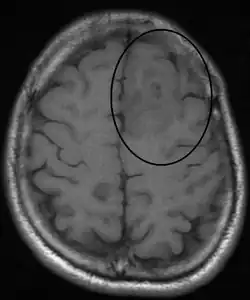

An oligodendroglioma as seen on MRI

Oligodendrogliomas are generally considered to be incurable using current treatments. However compared to the more common astrocytomas, they are slowly growing with prolonged survival. In a 2019 study, an 80% survival rate was reported at 15 years for 1p/19q co-deleted oligodendroglioma treated with upfront chemotherapy irrespective of tumor grade.[19]